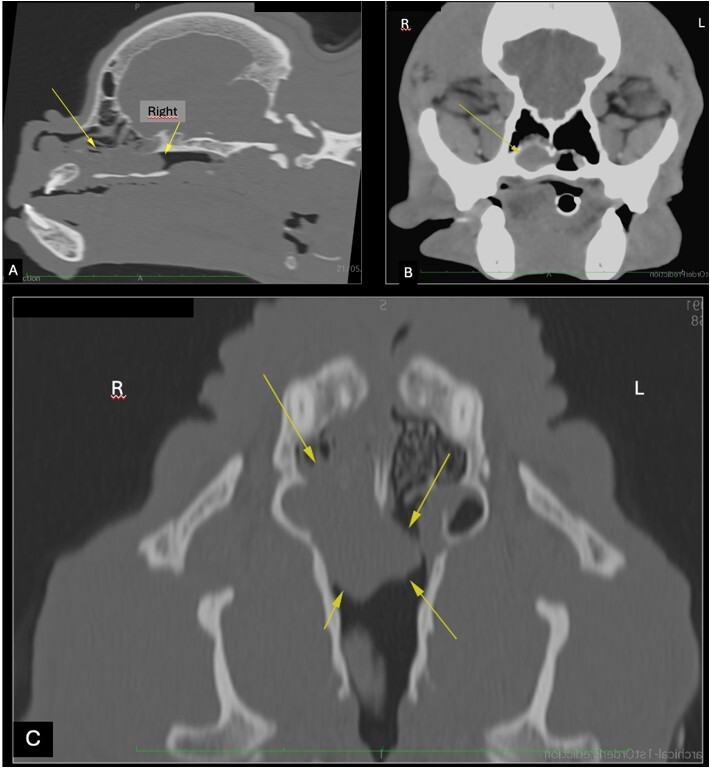

Epistaxis is defined as bleeding from the nasal cavity and can be related to systemic causes leading to coagulation disorders, most commonly hemoparasitosis, or to localized changes in the nasal cavity itself (e.g., intranasal neoplasms). Transmissible venereal tumors (TVT) are malignant round cell neoplasms characterized by an anomalous proliferation of tumor cells disseminated mainly by direct contact between animals. Although transmitted sexually, transmission through contact with mucous membranes and skin tissue can also occur, including the nasal cavity. Although rare, it can have significant clinical implications because it is difficult to diagnose. The diagnosis is made by physical examination, imaging tests (computed tomography and rhinoscopy), and histopathological analysis, which is the gold standard. Treatment is based on the use of chemotherapeutic agents, with vincristine as the drug of choice. This study reported a case of intranasal TVT in a 4-year-old French bulldog and addressed its clinical characteristics, diagnosis, and treatment. It also reported the importance of early recognition of the condition and changes in imaging tests to better understand and manage this atypical presentation.

Abstract Image